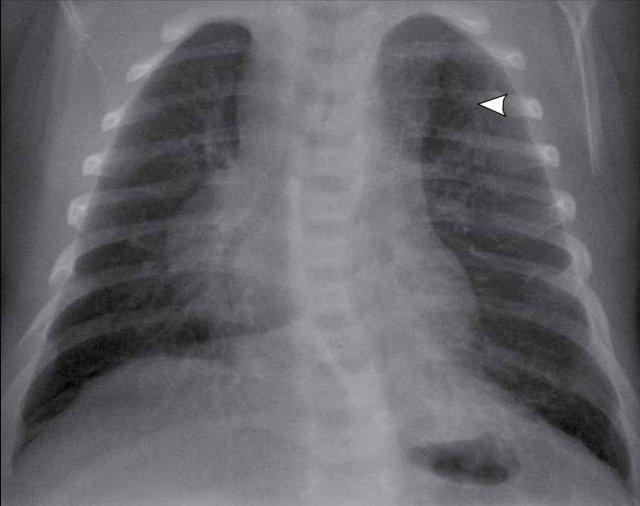

Hình ảnh

Trẻ 1 tuần tuổi, sinh ở tuần thai thứ 41.

Trên hình ảnh siêu âm tiền sản thường quy, phát hiện tổn thương dạng nang ở thùy trên bên trái.

Phim X-quang cho thấy vùng thấu quang được giới hạn rõ ở phần đỉnh của thùy trên phổi trái (mũi tên).

Có sự dịch chuyển trung thất nhẹ sang phải.

Chụp CT của bệnh nhân tương tự ở trên.

Tổn thương giảm tỷ trọng ở thùy trên phổi trái có dạng đa nang.

Do nang lớn nhất có đường kính hơn 2 cm, trường hợp này được phân loại là

CPAM type I.